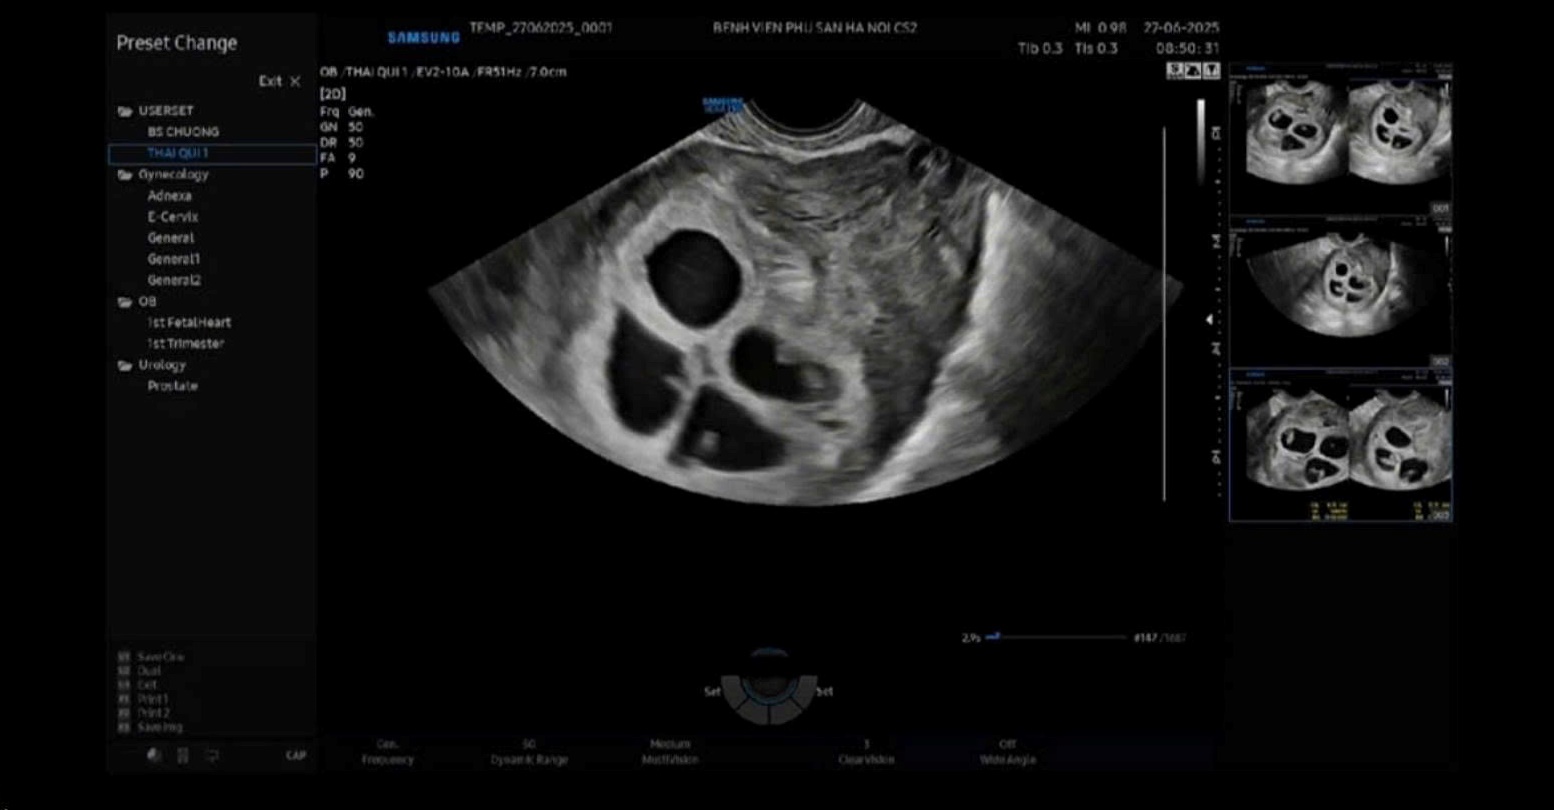

Kehamilan saat ini dipantau secara ketat oleh tim dokter berpengalaman, dengan indikator biologis lengkap dan gambar ultrasonografi yang menunjukkan bahwa keempat janin memiliki detak jantung, berkembang sesuai usia kehamilan, dan tidak menunjukkan tanda-tanda kelainan. Deteksi dini dan penanganan yang cermat sejak dini berperan penting dalam menjamin keselamatan ibu dan janin.

Penanganan kehamilan kembar spontan tidak hanya memerlukan keahlian tinggi, tetapi juga memerlukan pemantauan berkelanjutan dan koordinasi multidisiplin seperti kebidanan, resusitasi neonatal, nutrisi dan anestesi sepanjang kehamilan hingga kelahiran.